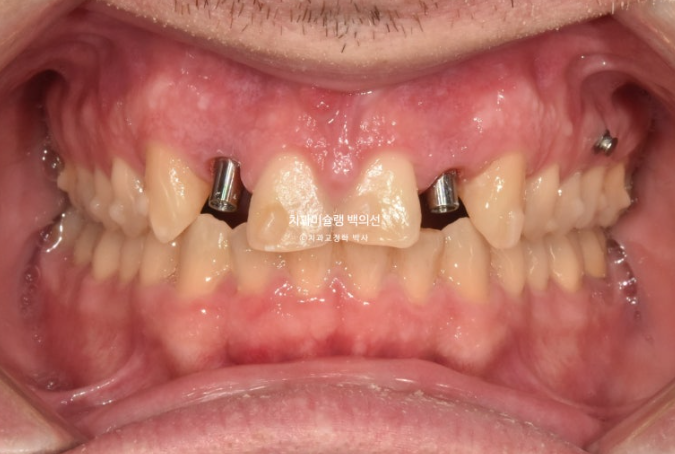

25.04

임플란트는 먼저 뿌리를 심고 몇달간 안정화 기간을 거쳐서 치아머리를 만듭니다.

약 6개월간 안정기간을 충분히 가진 후 25년 4월 임플란트 머리를 올립니다.

25.05

6개월의 기다리는 기간동안 환자분이 유지장치를 소홀히 끼셨는지 세워놨던 앞니 뿌리가 다시 약간 기울어졌죠

이 부분 개선을 위해 앞니 4개에 부분교저용 mta 장치를 붙이기로 했습니다.